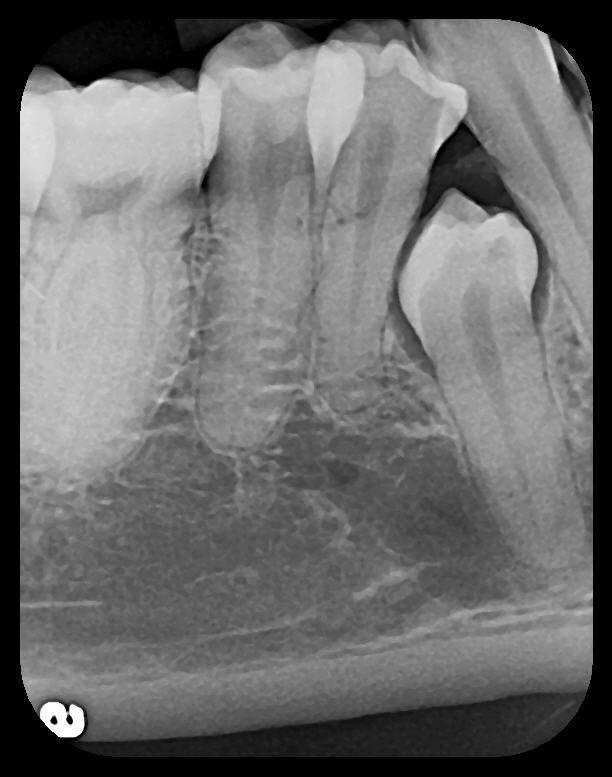

PSP sensor technology offers many advantages to the clinician in patient retention and workflow. The most important consideration is patient comfort and cooperation. PSP sensors are wafer-thin and flexible to allow placement in positions to capture third molar images without gagging or pain. The larger surface area of the most popular no. 2 size PSP sensor allows images of more dental anatomy (Figure 3); therefore, fewer exposures are necessary to create a full-mouth radiographic series. Their flexibility allows placement around tori and exostoses.1,9-12 The bite blocks, stabilizers, BW tabs, and positioning rings that were used for film radiographs will easily accommodate PSP sensor placement.

Some representative radiographic PSP images are exhibited here for demonstration of the anatomy and pathology that can be visualized with this technology. Many of these images would not have been possible if HW technology were used (Figure 3 through Figure 8).

As displayed here, the 2D radiographic images in Figure 3 through Figure 8 can alert the clinician to the need for a further 3D CBCT analysis to properly ascertain the anatomy and extent of the pathology that is initially visible in the intraoral radiographs. Proper treatment or referral to the appropriate specialty practice can follow.5,6 No. 2 PSP radiographs, when used in a conventional full-mouth series of radiographs on a patient with a relatively complete dentition, will routinely allow visualization of the anatomy of third molars, mandibular canal, maxillary sinuses, full dental root morphology, and bone anatomy beyond the apices2,16,17 (Figure 9 and Figure 10).

Fig 3. Two PSP PA radiographs of mandibular teeth showing: left, the initial view

of molar area and suspected pathology surrounding impacted tooth No. 32; center,

subsequently exposed PA radiograph, placed more distally, demonstrates extent

of large cyst as well as entire tooth and root No. 32. Proper alert as to presence

of suspected cyst and appropriate referral for 3D CBCT study and surgical

enucleation was given to the patient. Right: Same radiograph as on the left, but

with lighter superimposed outline of the area that would be visible using an HW

sensor rather than a PSP sensor. The small area of pathology is likely obscured

because it is visually overlaid by the root of tooth No. 31. Neglect of this significant

pathology may have resulted.

Figure 3